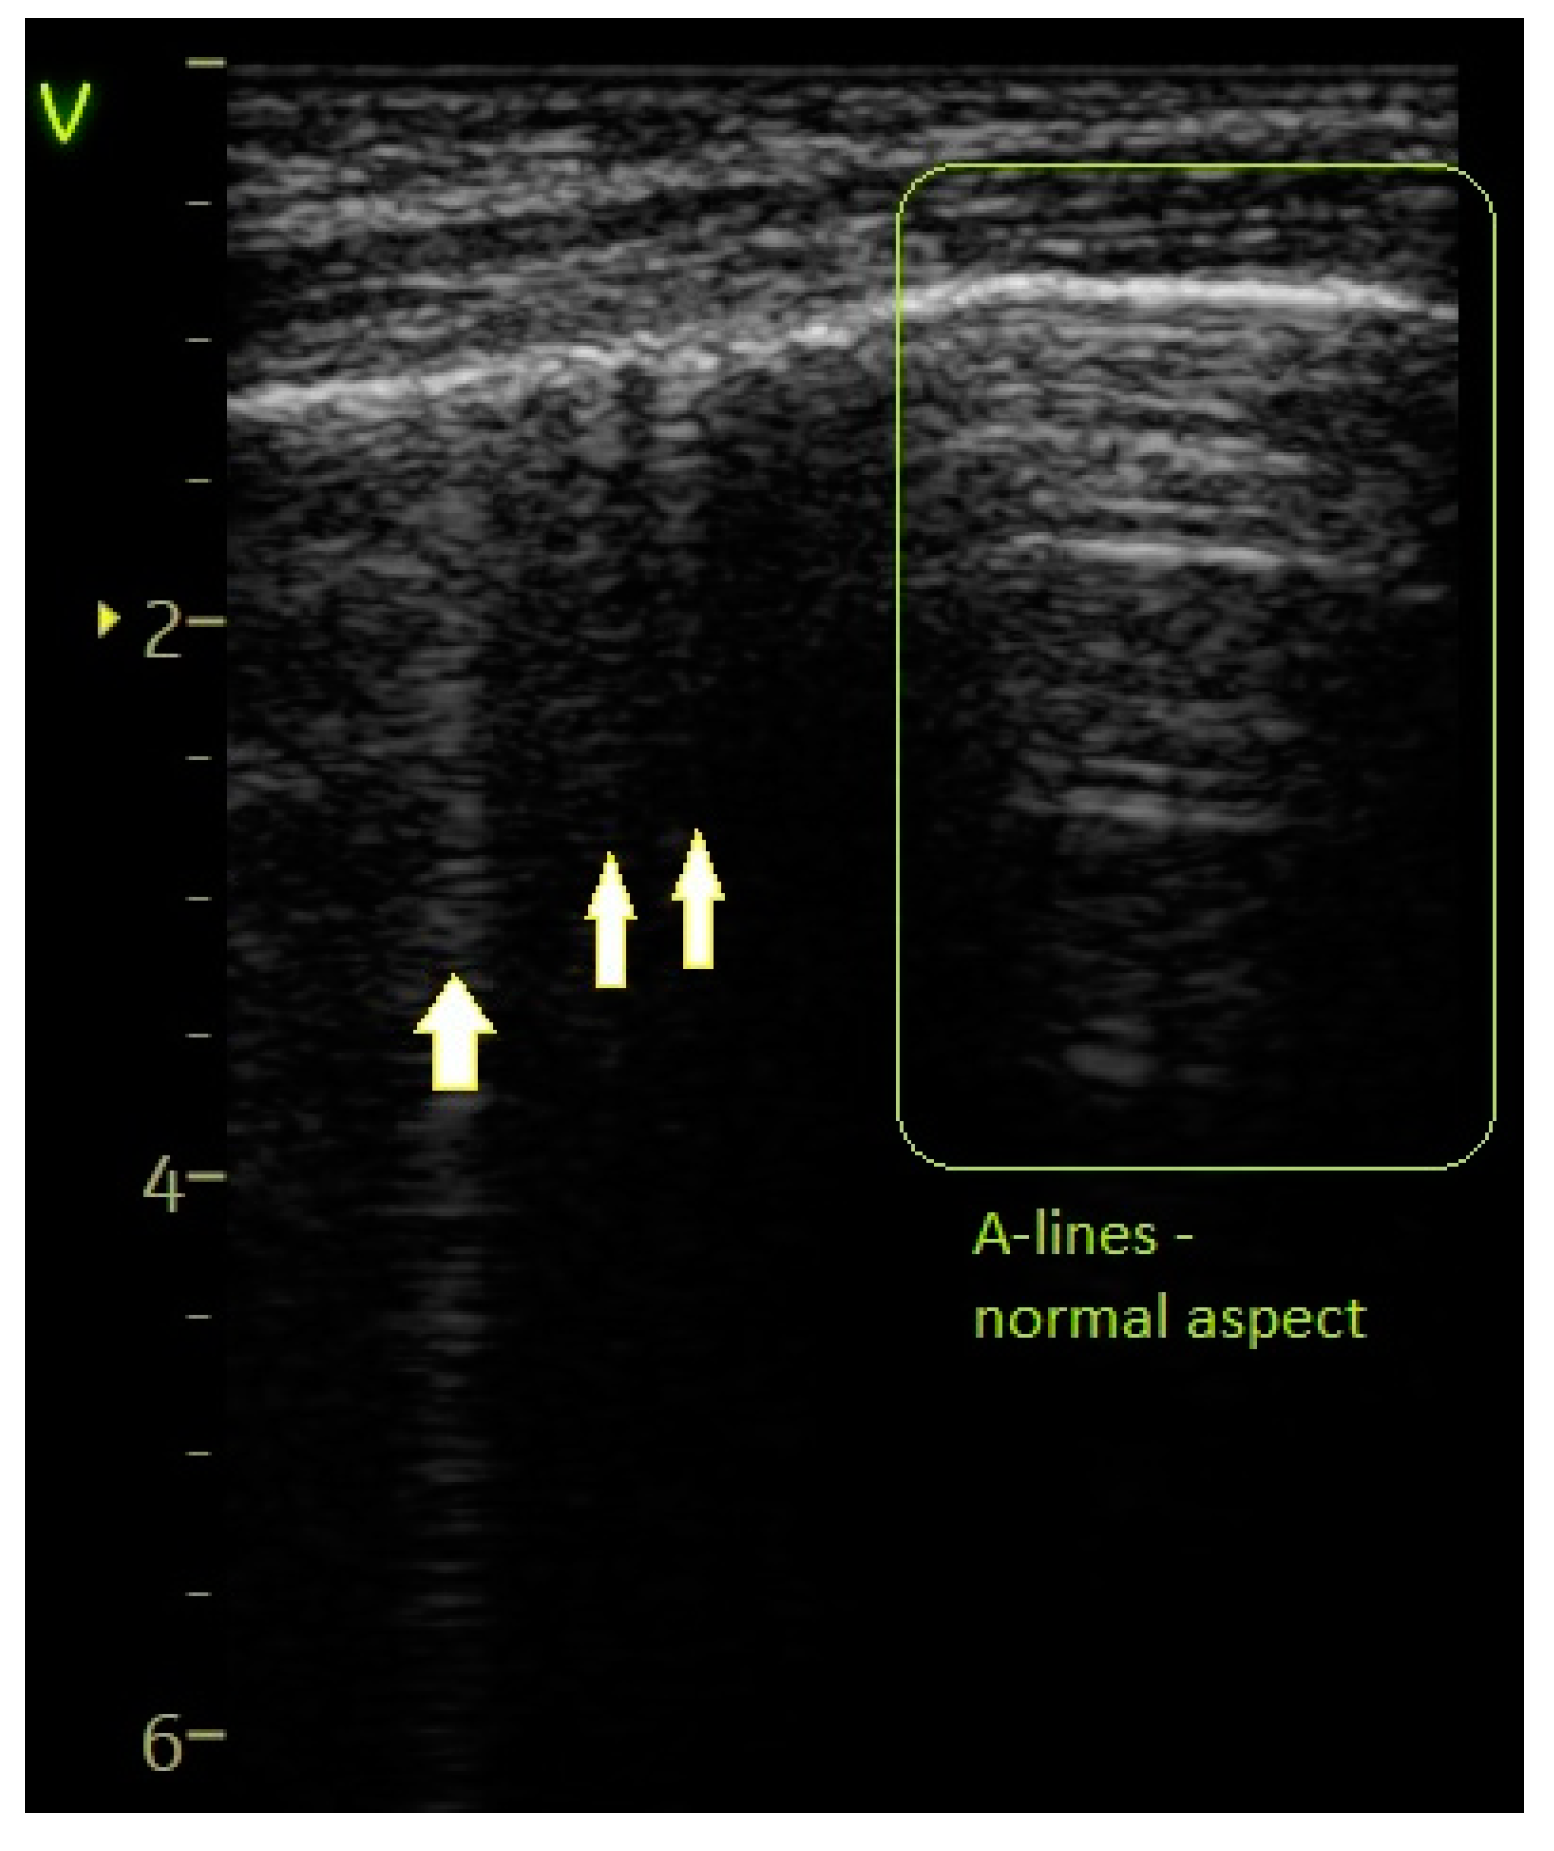

- A score of 0 was assigned for a normal or physiological pattern displaying A-lines, along with one or two B-lines per intercostal space.

| Sparse B-lines—Figure 3 | 55 (74.32%) | 11 (100%) | 25.68% | 3.59 | 0.0579 |